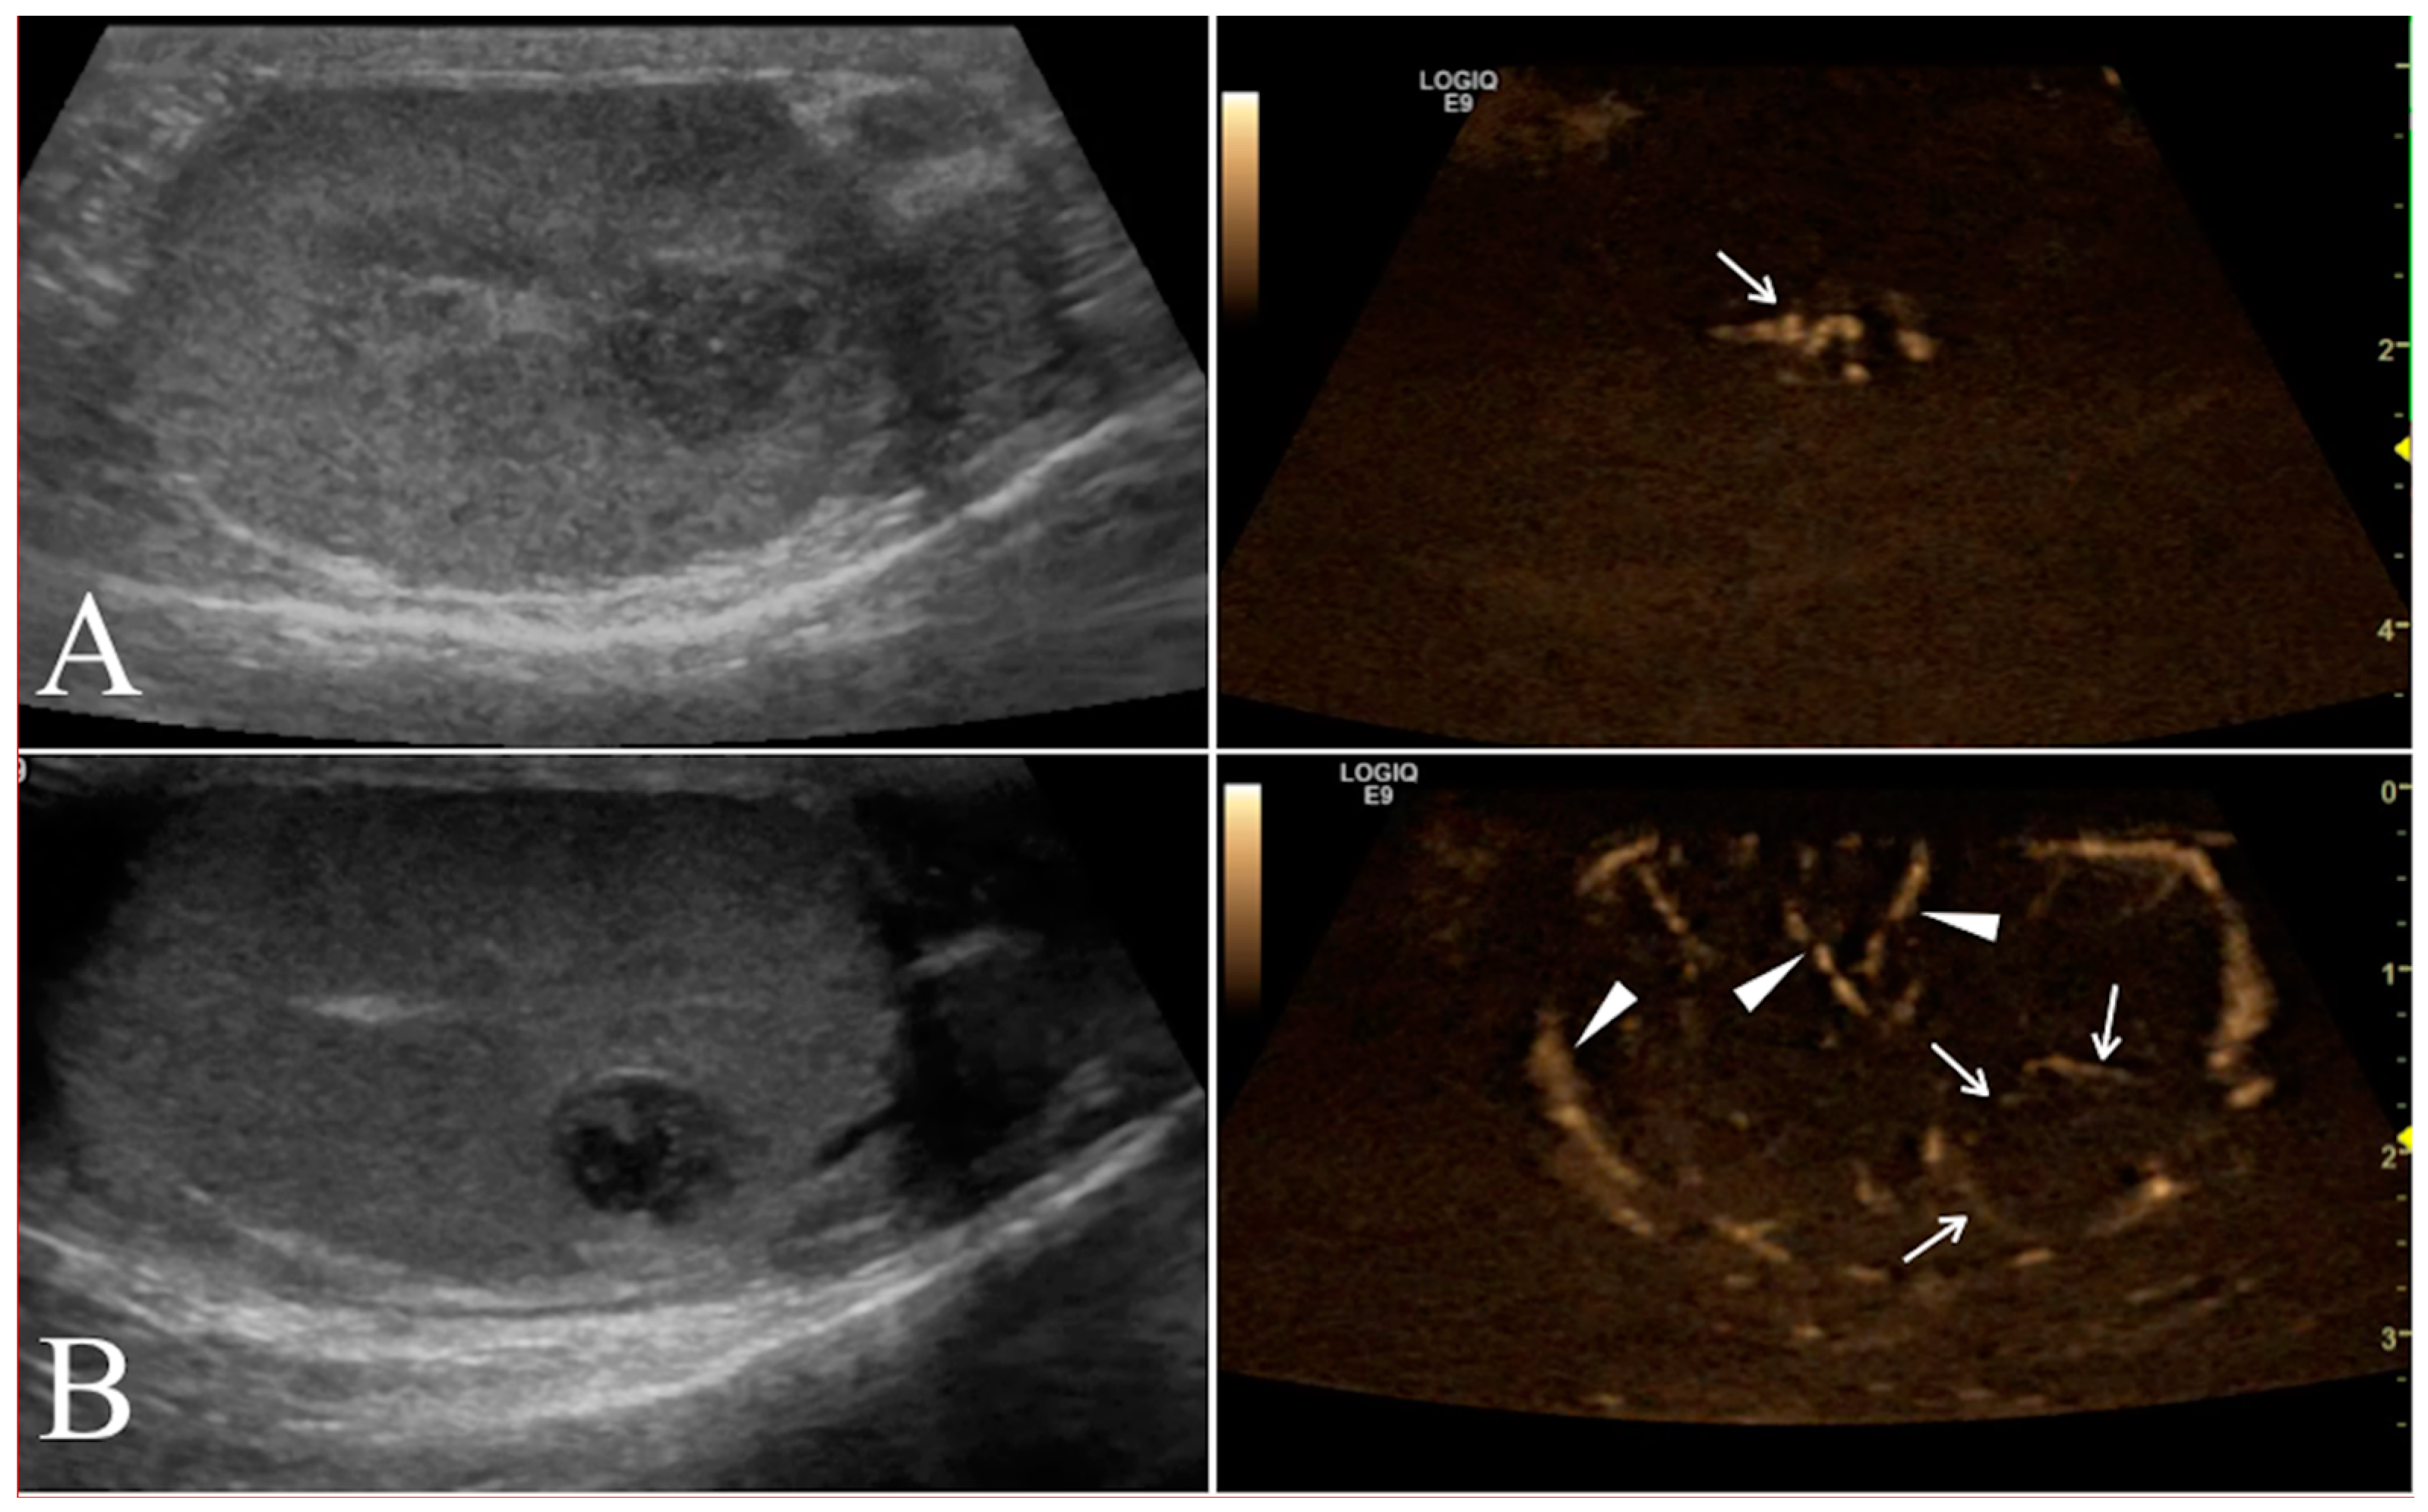

2.4. B-Flow Examination

B-flow examination was focused of the vascularization on the testicular tumor lesions. Once testicular parenchyma was visualized by B-mode, the system was switched to B-flow. Still images and video clips were saved for each location examined for subsequent analyses. The vessels of the tumor lesions were scored as 0, 1, or 2 if absent, smaller, or larger than 2 mm in diameter, respectively. Moreover, the vascularization was classified as P if the vessels were perilesional or I if distributed within the tumor lesion (Figure 3).

Figure 3. Conventional ultrasonographic scans (left panels) of two different seminomas found respectively in the right testicle of a 10 year old Labrador Retriever in (A) and in the right testicle of a 9.5 year old German shepherd in (B). In the right panel the B-flow images show the I distribution of the lesional vessels (arrow) scored as 2 in (A), while in (B) it was possible to record the P pattern of vessels distribution (arrows) scored in this case as 1. In this B-flow image, it is also possible to visualize some physiological testicular vessels (arrows head), represented by the marginal region and intra-testicular branches of testicular artery.